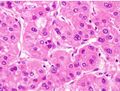

Pathology

Macroscopically, liver cancer appears as a nodular or infiltrative tumor. The nodular type may be solitary (large mass) or multiple (when developed as a complication of cirrhosis). Tumor nodules are round to oval, gray or green (if the tumor produces bile), well circumscribed but not encapsulated. The diffuse type is poorly circumscribed and infiltrates the portal veins, or the hepatic veins (rarely).[16]

Microscopically, the four architectural and cytological types (patterns) of hepatocellular carcinoma are: fibrolamellar, pseudoglandular (adenoid), pleomorphic (giant cell), and clear cell. In well-differentiated forms, tumor cells resemble hepatocytes, form trabeculae, cords, and nests, and may contain bile pigment in the cytoplasm. In poorly differentiated forms, malignant epithelial cells are discohesive, pleomorphic, anaplastic, and giant. The tumor has a scant stroma and central necrosis because of the poor vascularization.[39] A fifth form – lymphoepithelioma like hepatocellular carcinoma – has also been described.[40][41]

-

Well-differentiated HCC

Moderately differentiated HCC.

Poorly differentiated HCC